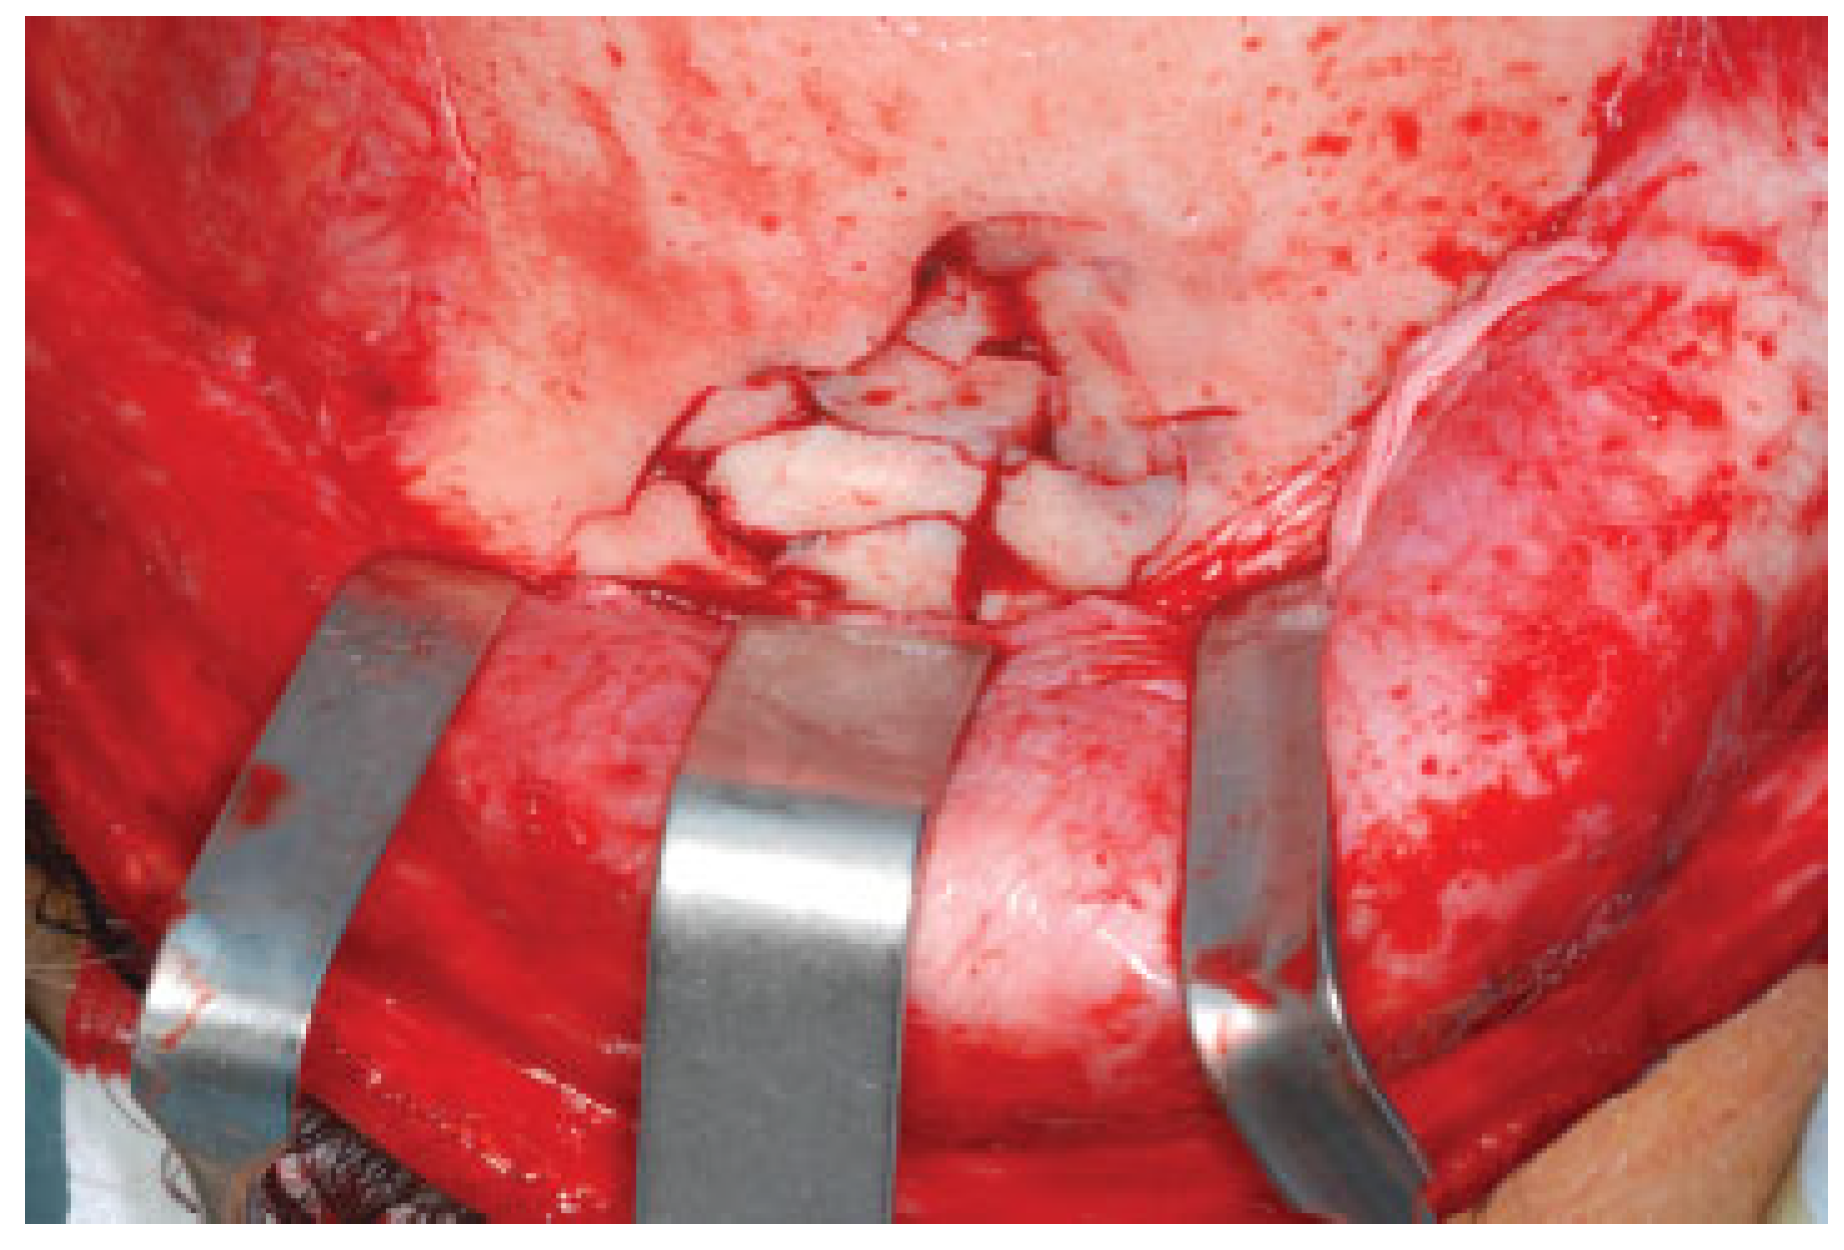

In all patients, a coronal approach was used to expose the comminuted frontal fracture (Figure 2). Titanium mesh was adapted to the defect and positioned as a template. The central portion of the mesh was then pressed into the defect so that its shape corresponded to the natural inner-table contour (Figure 3A,B). Each bone fragment was then fixed to the mesh with a mini-screw (Figure 4A,B). If nonstretching mesh is used, it must be contoured before it is fixed. After fixing all comminuted fragments, we removed the mesh and restored the frontal contour by simultaneously manipulating bone fragments and mesh (Figure 5A,B). Finally, we fixed the mesh to the intact frontal bone with mini-screws, thereby achieving a perfectly restored frontal sinus contour (Figure 6).

Figure 2. Preoperative view of the frontal fracture by coronal approach.